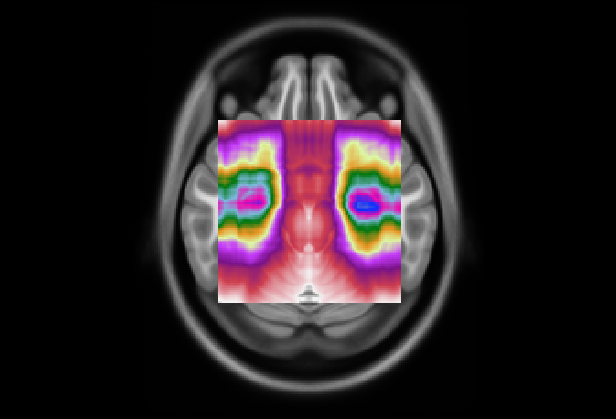

(a) Axial

Refer to caption

(b)

(c) Coronal

(d) Fold 1

(e) Sagittal

(f)

(g)

(h) Fold 2

(i)

(j)

(k) Fold 3

(l)

(m)

(n) Fold 4

(o)

(p)

(q) Fold 5

(r)

Figure 6: Average attention weight distributions generate by AwareNet model for each fold and each plane

We also analyzed the consistencies of AwareNet distributions (Wang et al., 2024) to compare the robustness and interpretability of different attention mechanisms. However, the average distributions produced by this model, as seen in Fig. 6, present sparsely distributed peaks and do not allow the identification of predominant slice ranges. Furthermore, the distributions between the folds are inconsistent. These results indicate that in this case study, AwareNet could not produce consistent attentional weights useful for contributing to the interpretability of its decisions.